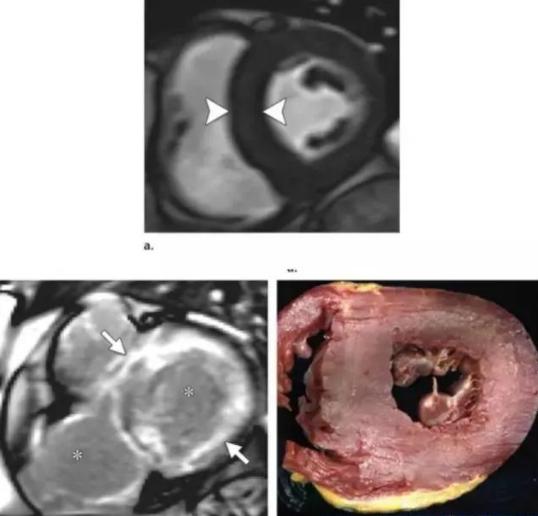

然后告诉年轻的医生们:“患者心脏彩超提示高血压性心脏病改变,心脏增大,那么心电图应该是高电压改变。但是患者的心电图却是出现了低电压和病理性q波,说明心电图与实际的心脏结构不匹配,这就是其中的问题所在。那么什么疾病会导致这种情况呢?”

经过主任这么一提醒,年轻的医生们茅塞顿开。主治医生立马说道,患者已经排除了胸腔积液和心脏积液,那么就只有心肌淀粉样变性有最大可能了。但是也要考虑脚气性心脏病的可能。

主治医生立马答道:“淀粉样物质在心脏中沉积、浸润,多种蛋白质形成独特的铰链状β褶形片层纤维沉着,男性多于女性,在30岁以前很少见到。因此这是一个老年性疾病且具有明显的遗传性。淀粉样变性是一大类疾病,通过不同的发病机制,由多种蛋白质形成独特的铰链状β褶形片层纤维沉着所致。淀粉样蛋白几乎可见于任何器官,但一般不会发生广泛的浸润,一般来说,心脏、肾脏、肝脏和周围神经是心肌淀粉样变最常累及的脏器,因此患者可以出现呼吸困难、下肢水肿等表现。”